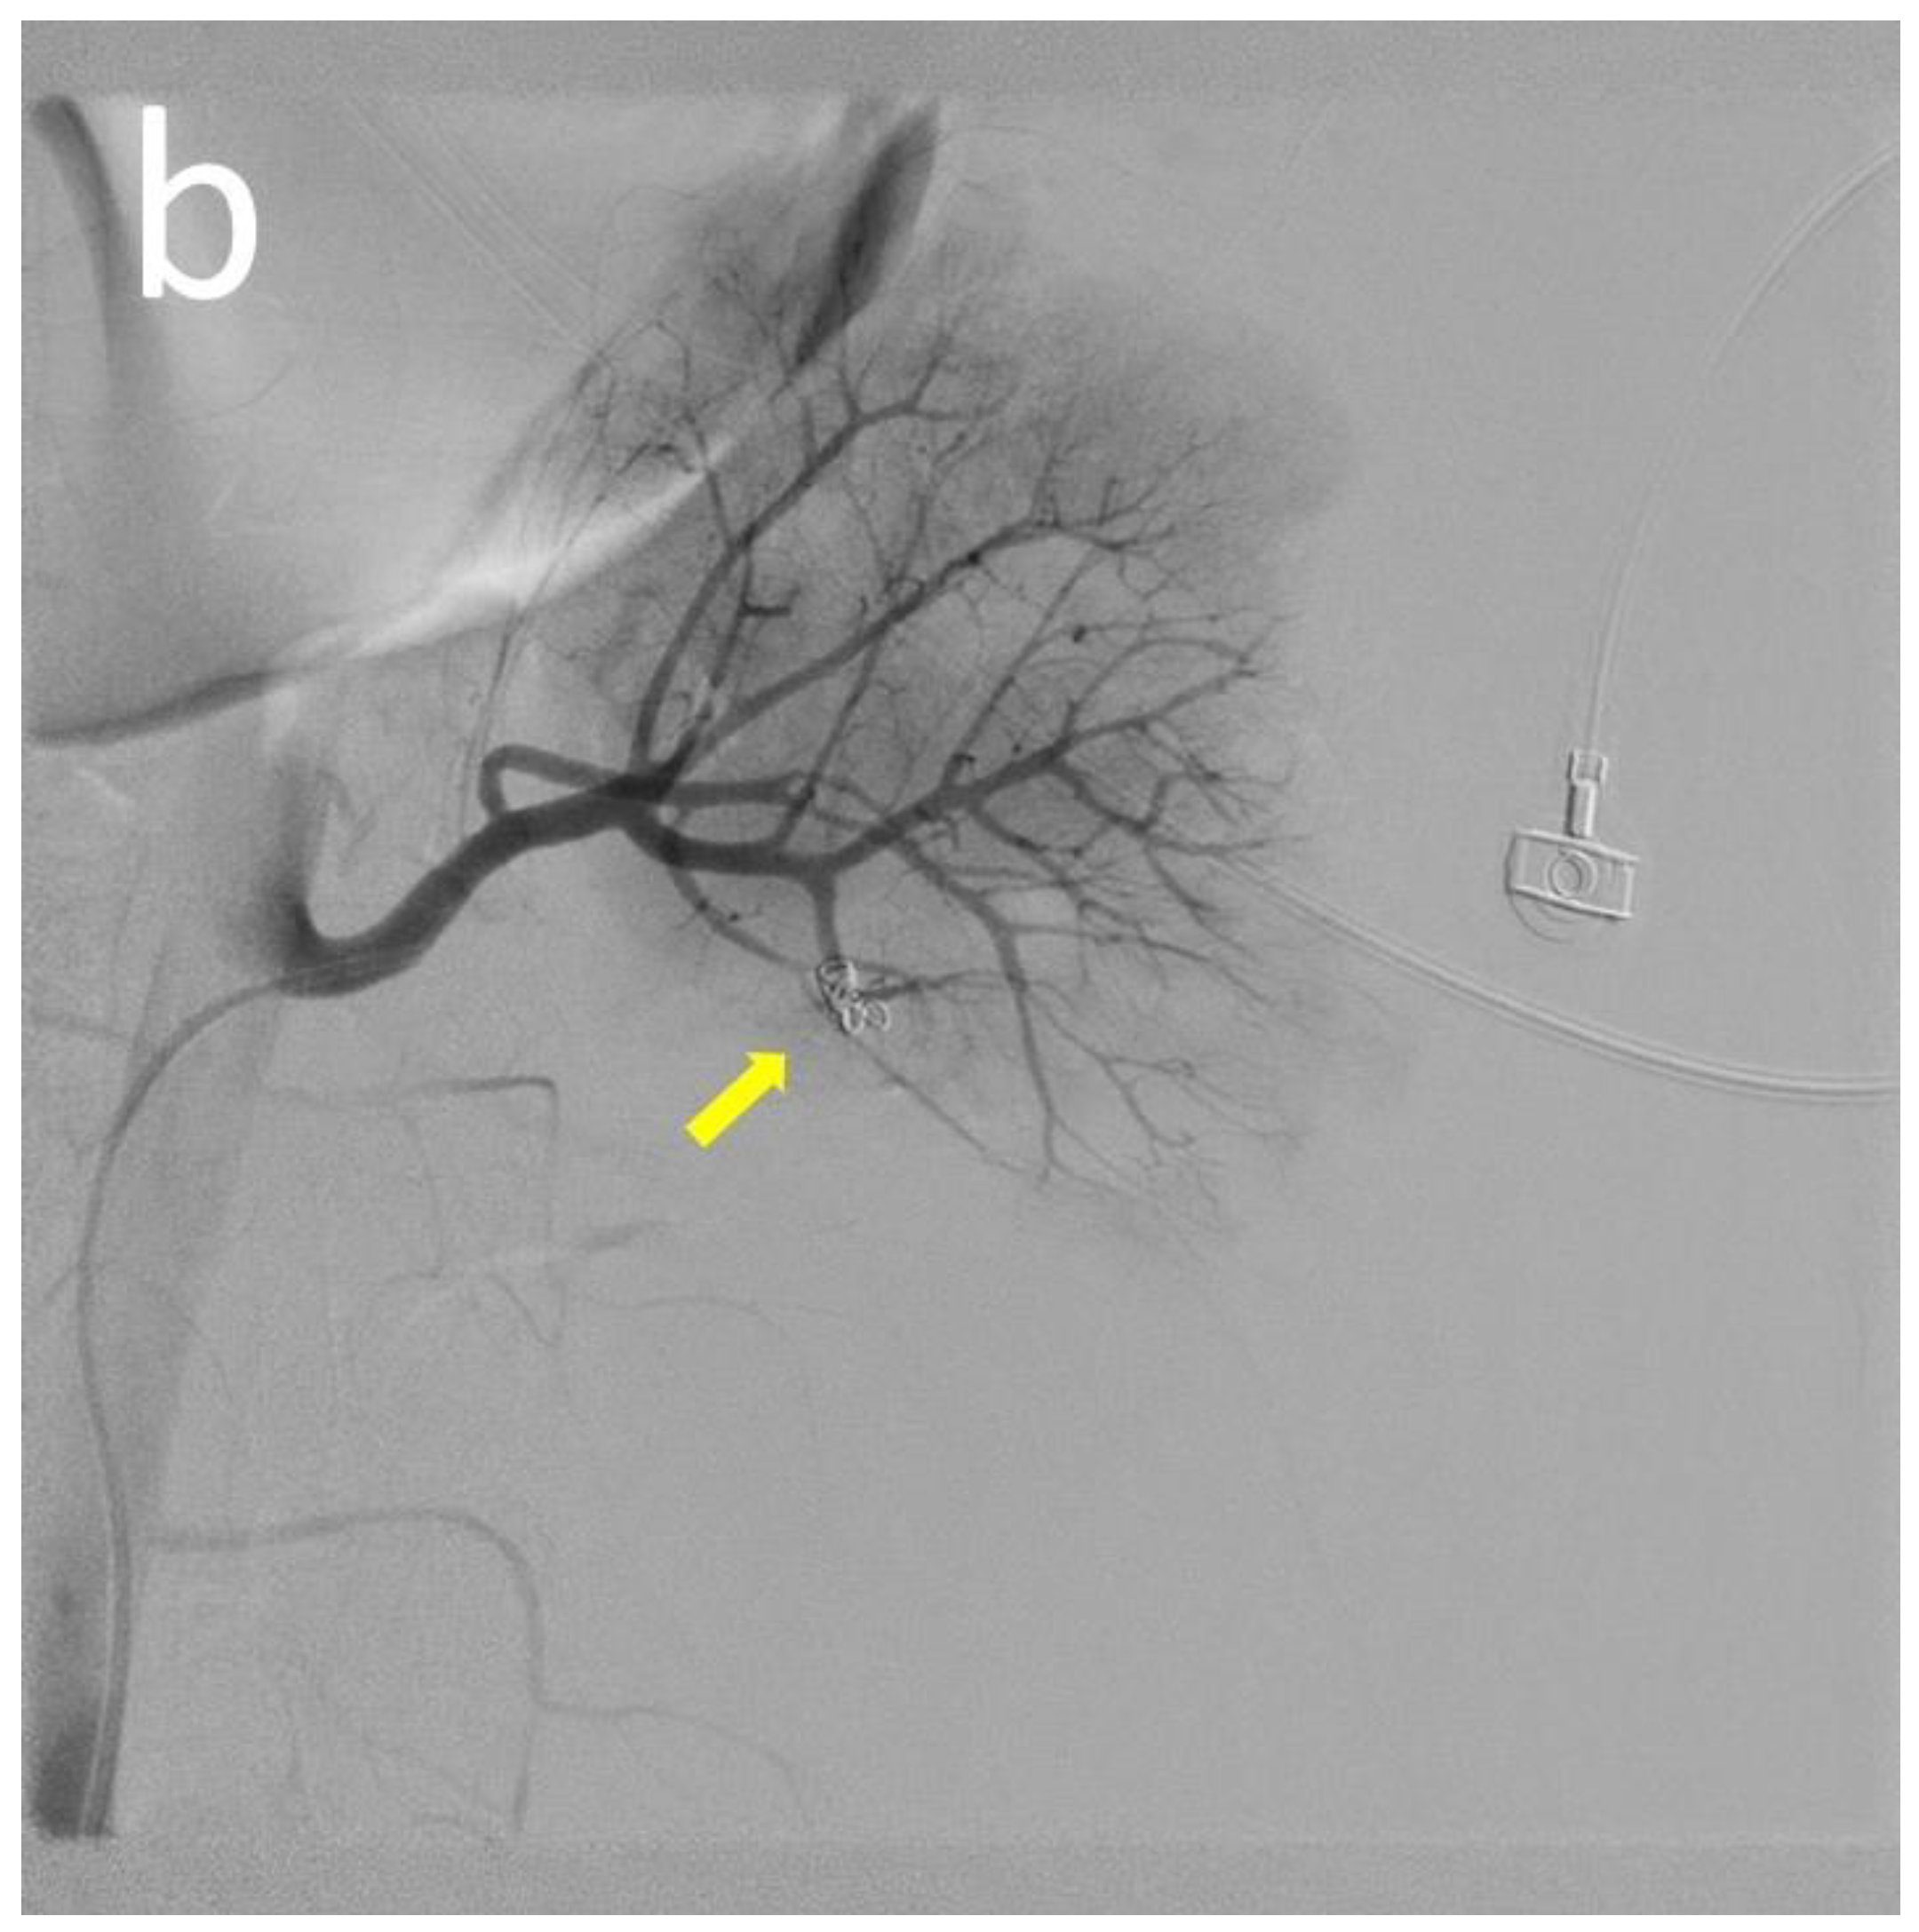

| 13 | Our case | 18 | Male | 12 | Flank pain Anemia(Hb: 6.7 g/dL) | Normal | Normal | CT | Angiodysplasia of the left renal artery & branch of IMA | N/A | Anti-dsDNA antibody Lupus anti-coagulant Anti-cardiolipin IgM | Embolization Steroid | N/A | Alive |